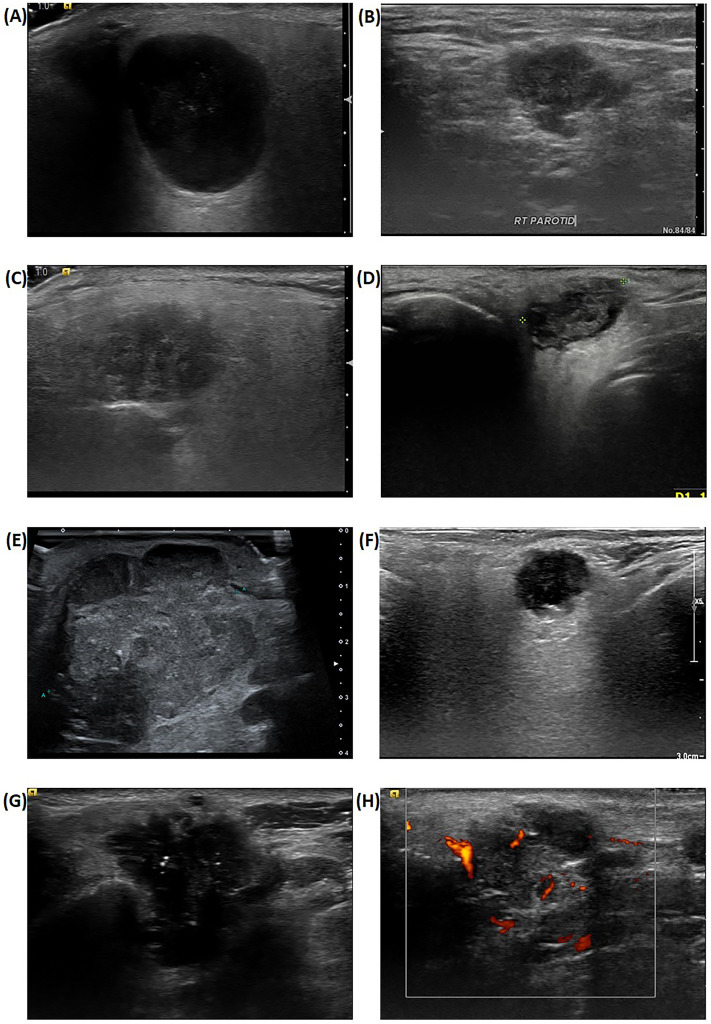

目的高分辨率超声检查(US)的最新进展使其成为评估腮腺病变的重要工具。然而,缺乏标准化的诊断标准限制了超声在确定恶性肿瘤中的应用。本研究探讨US作为腮腺癌预后因素的潜在作用。方法将2016年1月至2022年12月在我院三级转诊中心确诊并接受手术治疗的腮腺癌患者纳入回顾性队列研究。我们回顾性地获得了患者资料,包括US图像和临床因素,并分析了它们与各种不良特征和肿瘤预后的相关性,包括五年无病生存期(5Y DFS)和总生存期(5Y OS)。结果共纳入126例患者。5Y的DFS和OS分别为81.7%±3.7%和81.2%±4.1%。多变量分析显示,年龄(DFS;HR 2.75 [1.76-4.29], p =。023年,操作系统;HR 3.38 [2.06-5.54], p = 0.014),临床结期(DFS;HR 5.87 [3.74-9.21], p p p =。019年,操作系统;HR 0.34 [0.20-0.57], p = 0.037)为显著变量。在早期腮腺癌患者中,手术的程度对治疗结果没有影响。结论超声后路增强是腮腺癌预后的有利因素。对于表现出后部增强的早期癌症患者,最小化手术范围并不会影响肿瘤预后。

ObjectiveRecent advancements in high-resolution ultrasonography (US) have established it as a critical tool for evaluating parotid lesions. However, the lack of standardized diagnostic criteria limits the utility of US in determining malignancy. This study investigates the potential role of US as a prognostic factor in parotid cancer.MethodsPatients diagnosed with and surgically treated for parotid cancer at our tertiary referral center from January 2016 to December 2022 were included in this retrospective cohort study. We retrospectively obtained patient data including US images and clinical factors and analyzed their correlation with various adverse features and oncological outcomes, including five-year disease-free survival (5Y DFS) and overall survival (5Y OS).ResultsA total of 126 patients were included. The 5Y DFS and 5Y OS were 81.7% ± 3.7% and 81.2% ± 4.1% respectively. Multivariate analysis revealed that age (DFS; HR 2.75 [1.76-4.29], p = .023, OS; HR 3.38 [2.06-5.54], p = .014), clinical nodal stage (DFS; HR 5.87 [3.74-9.21], p < .001, OS; HR 9.34 [5.48-15.91], p < .001) and the presence of posterior enhancement artifact on US (DFS; HR 0.33 [0.21-0.53], p = .019, OS; HR 0.34 [0.20-0.57], p = .037) were significant variables. In patients with early-stage parotid cancer who showed posterior enhancement, the extent of surgery did not affect treatment outcomes.ConclusionPosterior acoustic enhancement on ultrasonography is a favorable prognostic factor in parotid cancer. For patients with early-stage cancer who demonstrate posterior enhancement, minimizing the extent of surgery does not compromise oncologic outcomes.